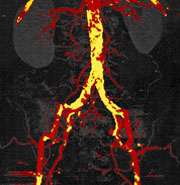

The dual energy imaging with facilitated bone and plaque removal significantly improves diagnostic confidence of CT angiographic imaging of the entire vascular territory. This technique is particularly helpful in patients with advanced atherosclerosis, when conventional CT angiograms are difficult to interpret.

The Dual Source CT scanner enables the simultaneous operation of the two X-ray sources at two different energy levels (dual energy mode). It therefore allows the acquisition of two data sets of diverse information. Because X-ray absorption is energy-dependent, changing the energy level of the X-ray source results in a material-specific change of attenuation. The material-specific difference in attenuation facilitates differentiation, characterization, isolation, and distinction of the imaged tissue and material. Furthermore, specific details of the scanned body part beyond morphology can be obtained.

In this context, the dual energy technique has markedly simplified bone removal on cerebrovascular, abdominal and peripheral run-off studies, replacing a laborious and time-consuming manual chore by an easy step that takes less than a minute to perform on a workstation for image analysis and post-processing.

In addition, based on a newly developed software algorithms, the dual energy technique allows the automated removal of calcified plaque from the vessel. This permits to readily detect and display narrowed segments of the arterial tree otherwise obscured by overlying calcifications without time-consuming manual post-processing. This technique is particularly helpful in patients with advanced atherosclerosis, when conventional CT angiograms are difficult to interpret.

Overall, dual energy imaging with facilitated bone and plaque removal overcomes limitations of standard CT, improves diagnostic confidence of CT angiographic imaging of the entire vascular territory and is expected to improve patient care.